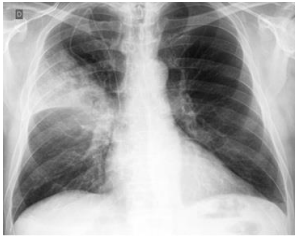

Podemos observar, nitidamente, nesta radiografia, um infiltrado à direita, compatível com uma consolidação lobar, o que configura: